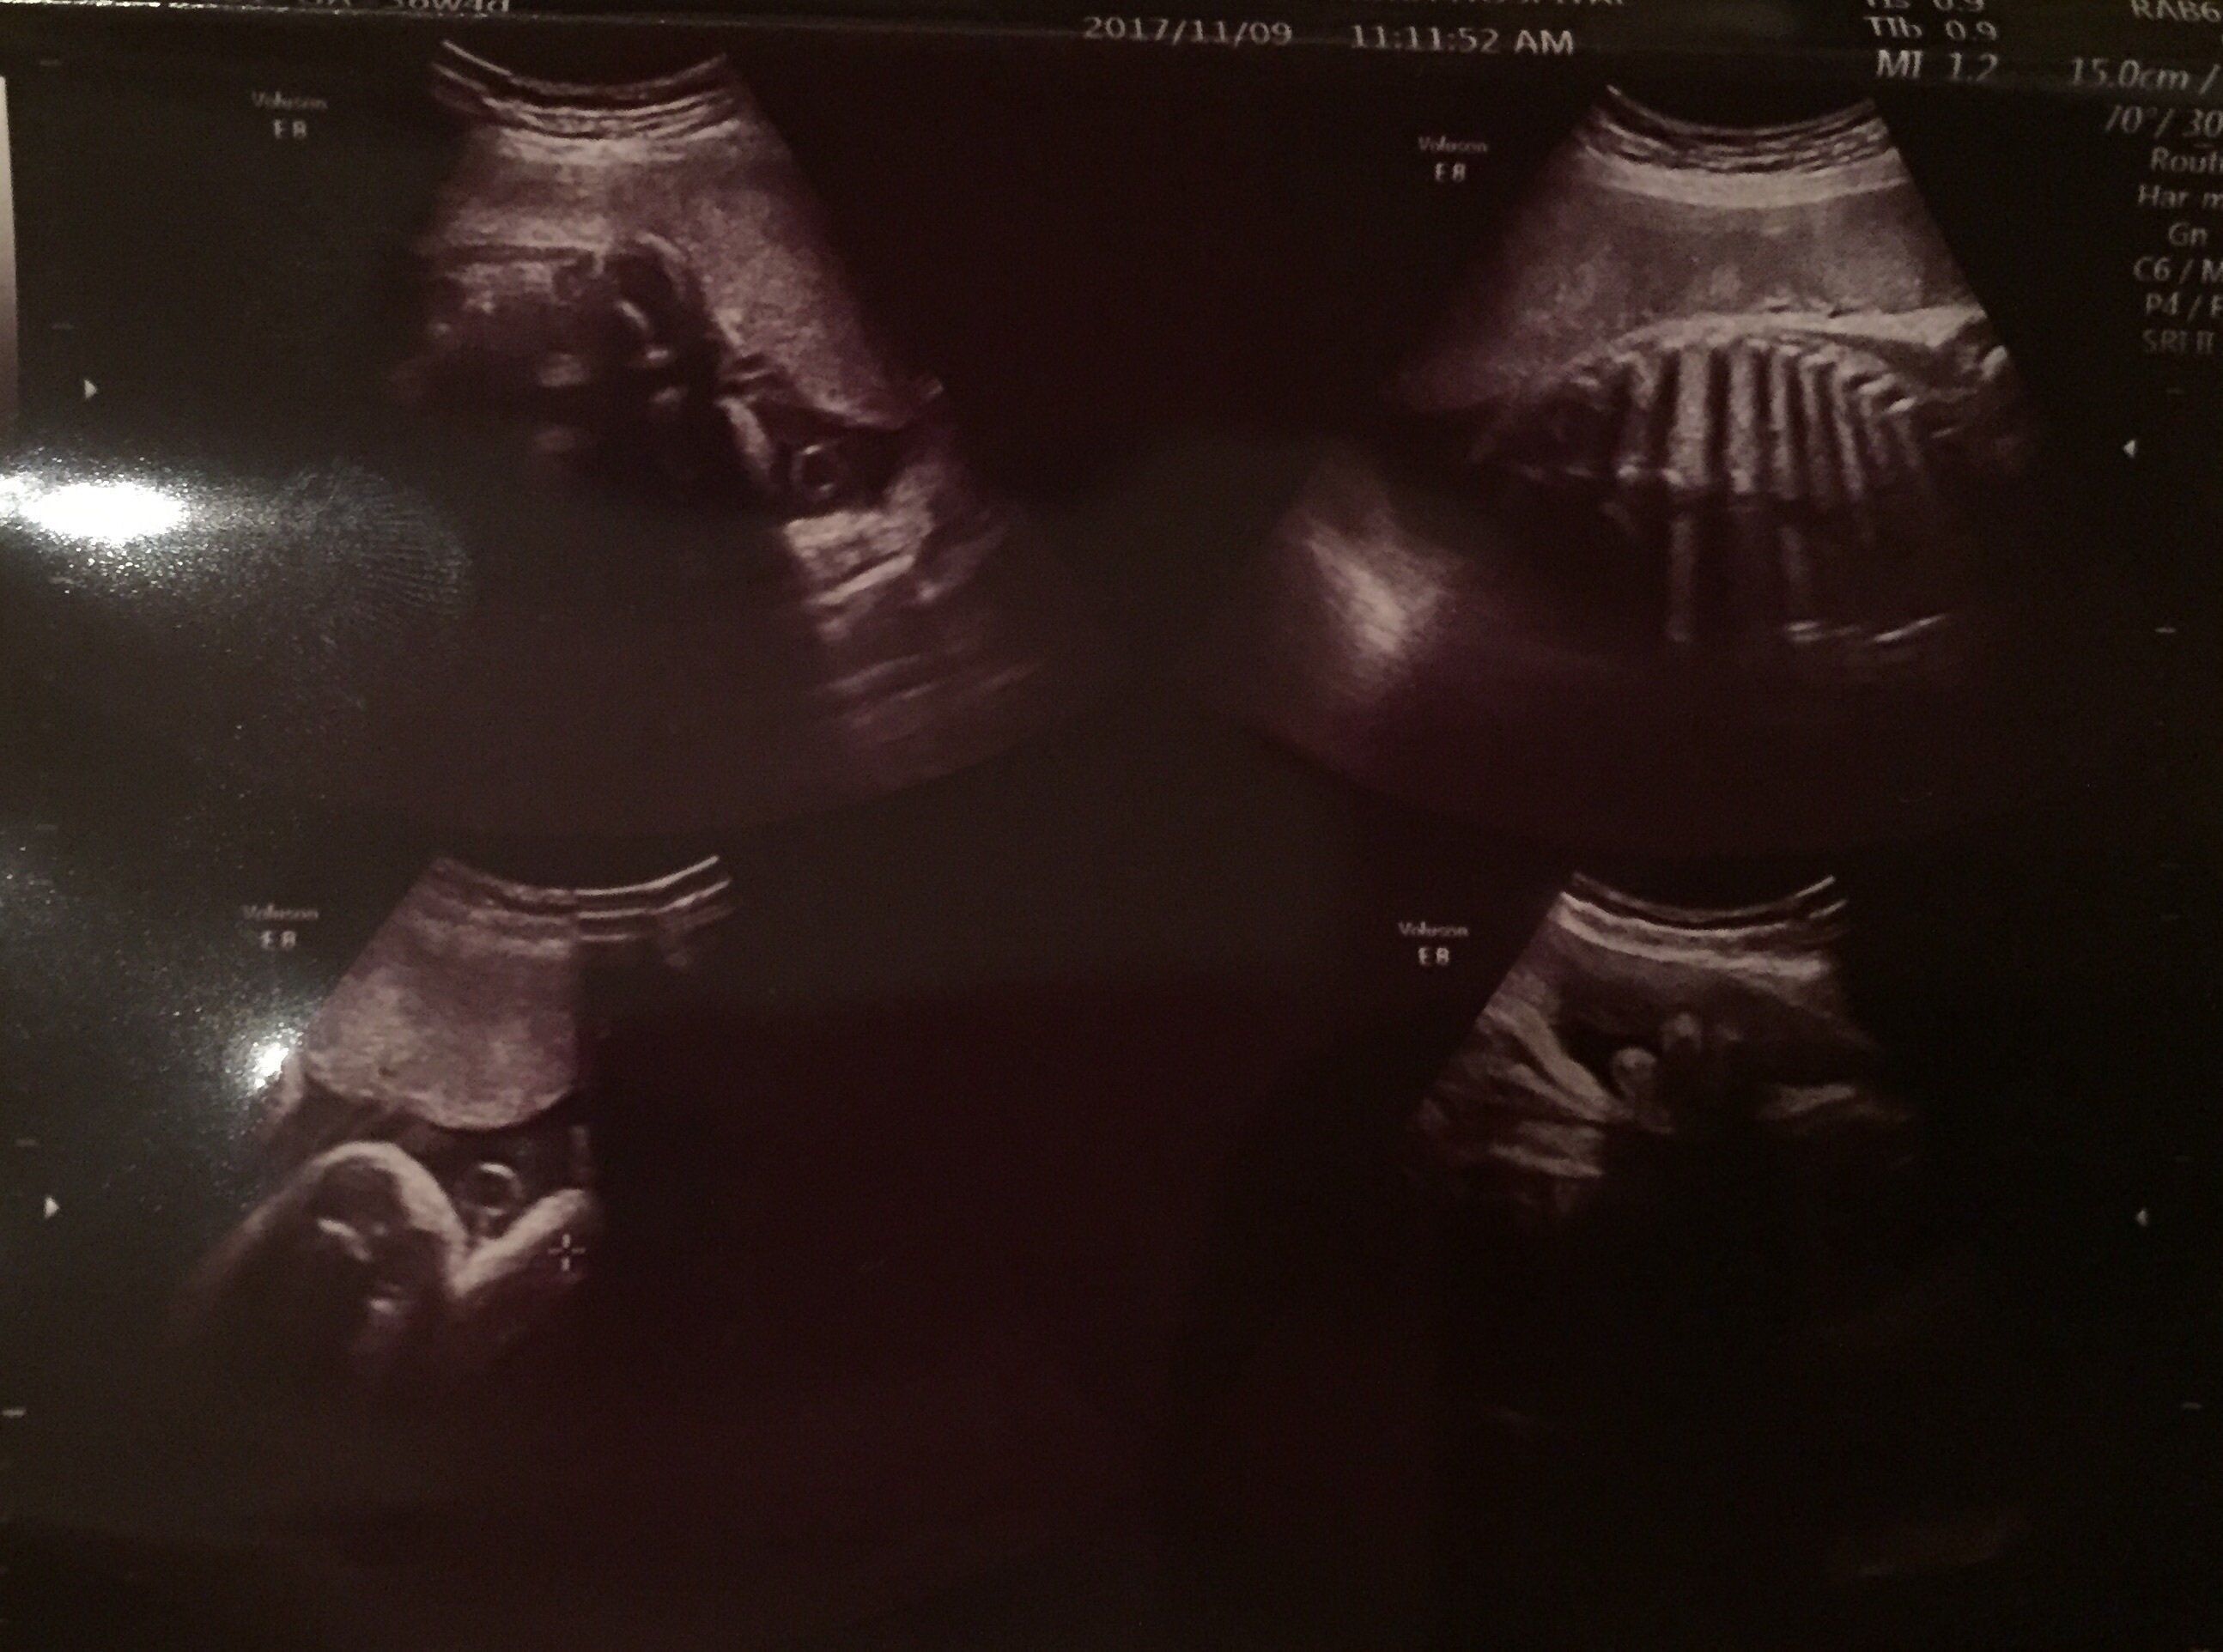

前回の健診で性別は男の子とほぼ…というか確実にわかっていましたが、このときの健診では前回と先生が違っていたため、また「前回、性別聞いたかな? 間違いなくこれ男の子だね」、「そうですよね、ついてますもんね、立派なのが…笑」という会話がありました。両足の間にシンボルがはっきり見えています。これは、足のちょうど真下から撮影した写真です。

つい足の間にばかり目がいきがちですが、前回と比べると太もももだいぶお肉がついて丸みを帯びてきたのがわかります。2週間でも成長がみられ、嬉しくなりました。このころの私は健診のときに、連続で“尿たんぱく”もしくは“尿糖”が見られ、食生活の改善を命じられていました。「塩分控えめで」と言われても、もともと我が家は薄味…。水分補給を意識的にすることで改善しようと毎日たくさん水を飲むようにしていました。